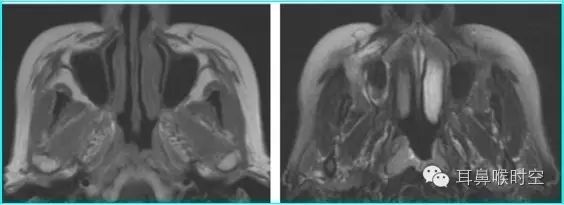

MRI

根据经典Fujioka 等 X 线平片测量法原理:

A/ N 比:测量腺样体最大厚度与自硬腭上缘到颅底蝶枕骨的软骨结合部的距离之比

PAS:后气道间隙(pharyngealairway space , PAS)的宽度(软腭表面与腺样体表面之间有效气道宽度)。

采用SE 序列矢状面T1WI

选择正中矢状面,分别测量两条径线(图1、2)

N 线:即从蝶骨体2枕骨斜坡的软骨结合部后缘(O点)至硬腭与软腭上缘交界处的连线N

A 线:过O点沿枕骨斜坡下缘作延长线L,取腺样体下缘最凸点作L线的垂直线。

A/N比:分别测A、N值,计算A/N 比

正常组镰刀形(图4)、刀鞘形(图5)为主

镰刀形、刀鞘形,腺样体厚度较薄,下缘凹陷或平直,但均不下凸

肥大组子弹形(图6)、山丘形(图7)为主

肥大组:子弹形、山丘形,腺样体饱滿、下凸,象山丘样突出。在冠状面上腺样体表现为“马鞍形”和“倒置梯形”。

解剖结构:在MRSET1WI 鼻咽部正中矢状面图像上,由于采取薄层断面成像

可以直观显示腺样体本身

清晰显示蝶骨体与枕骨斜坡之间的软骨接合部、鼻后孔间隙、鼻甲、硬腭与软腭上缘的交界面、软腭、会厌软骨等结构

易于测量:非常容易画出A 线及N 线,及测量PAS,了解鼻后孔间隙、鼻甲大小、软腭厚度及后突程度

MRI表现:

多方位检查

有利于显示肥大的腺样体

呈等T1、长T2信号

增强时可强化